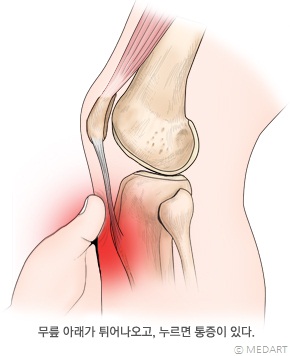

무릎 바로 아래, 정강뼈 위쪽의 앞부분이 툭 튀어나오고, 누르면 아프며, 운동을 한 뒤에 통증이 생기는 질환이다. 초등학교 고학년에서 중학교 저학년 사이에 흔히 발생하며, 아무래도 활동량이 많은 남자 아이에게서 더 흔하다. 증상의 정도는 신체 활동량과 비례하고, 무릎 양쪽 또는 한쪽에 발생한다.

무릎 바로 아래, 종아리뼈 위쪽의 앞부분이 툭 튀어나오고 활동 증가와 비례한 병변 부위의 압통이 있다.

오스굿슐라터병의 증상